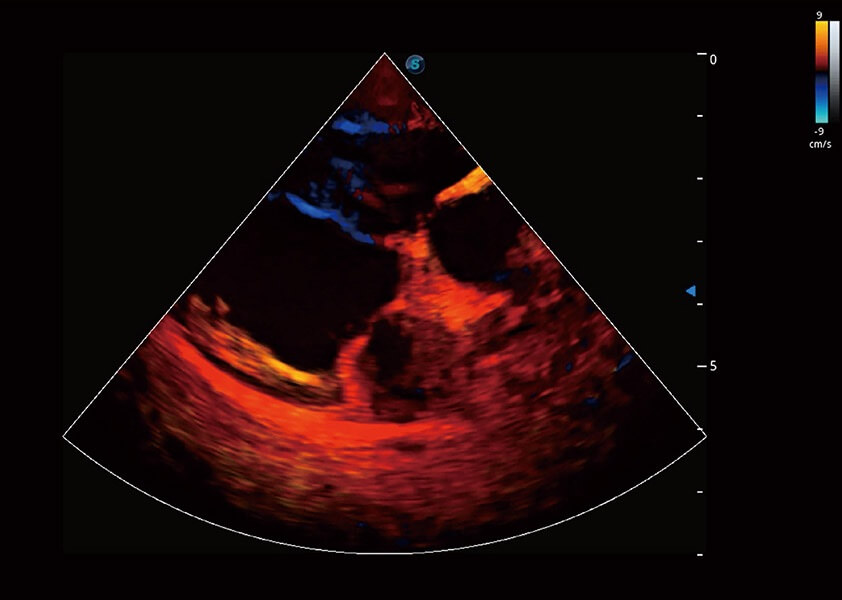

ProPet 60 作为一款高端台式动物超声设备,为动物医生的日常诊断提供了一系列贴合动物临床需求、解决临床实际问题的高级成像功能。凭借全系列高清探头,满足医生对腹部、心脏、生殖、浅表、肌骨等成像的所有需求,切实帮助您提升检查效率,提高诊断信心。

动物是人类最亲密的朋友和最值得信赖的伙伴。银河集团官网也一直致力于探索动物专用的超声影像解决方案。 全新推出的ProPet系列,是银河集团官网在动物超声影像智能化、专业化、精准化的一次跨越式革新。动物不能用言语来表述自己的不适,通过超声影像,ProPet系列搭建了动物医生与不同物种沟通的“桥梁”,为动物医生注入了“治愈之力”。